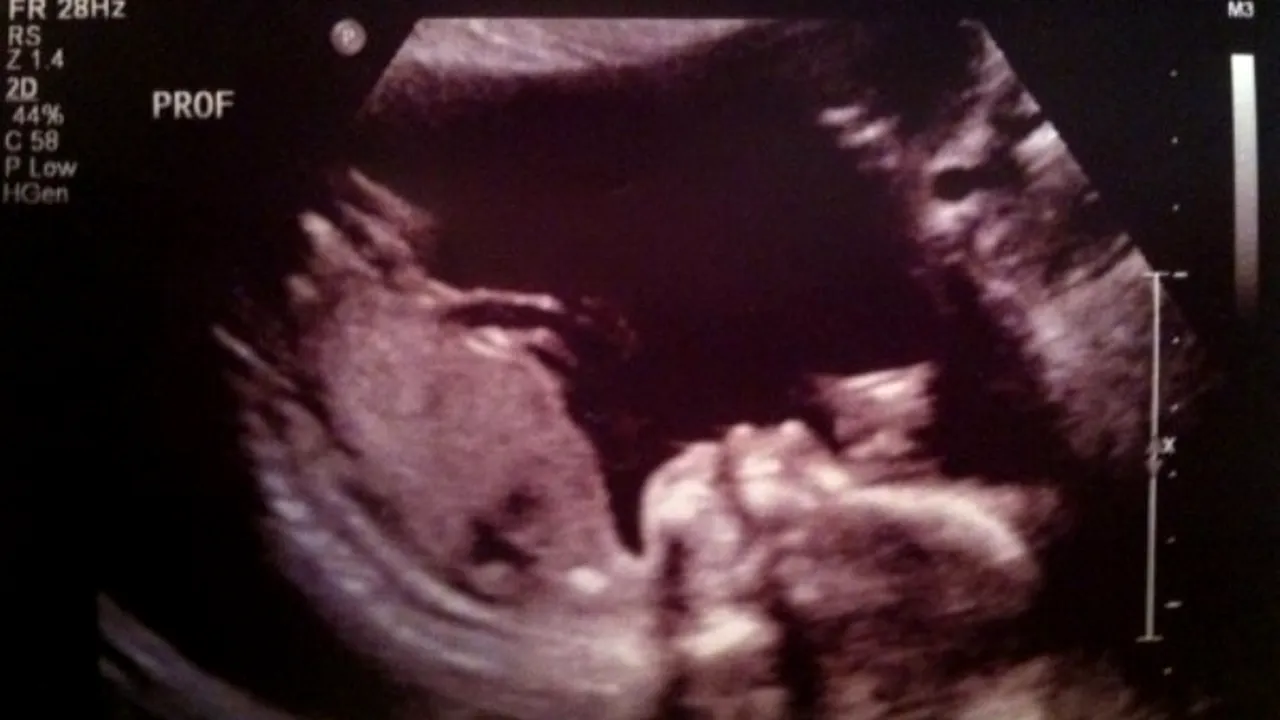

O viitoare mamică din Marea Britanie a trecut prin clipe de șoc, după ce a mers să facă o ecografie de rutină. Femeia a fost aproape sigură că a văzut pe ecran, lângă bebelușul ei „conturul unui extraterestru".

Sophie Scott, 16 ani, a mers la medic să facă o ecografie, fiind foarte nerăbdare să vadă ce face viitorul ei bebeluș. Lucrurile nu au decurs așa cum se aștepta tânăra, acesta speriindu-se teribil în momentul în care a văzut pe ecran ceva ce semăna cu „chipul unul extraterestru”, relatează Mirror.

„Am mai văzut un chip lângă bebelușul nostru, iar forma capului semăna exact ca cea a unui extraterestru. Am fost un pic speriați, dar apoi ne-am amuzat de situație. Cu toate acestea, nimeni nu și-a putut da seama despre ce a fost vorba, de fapt”, a mărturisit britanica.